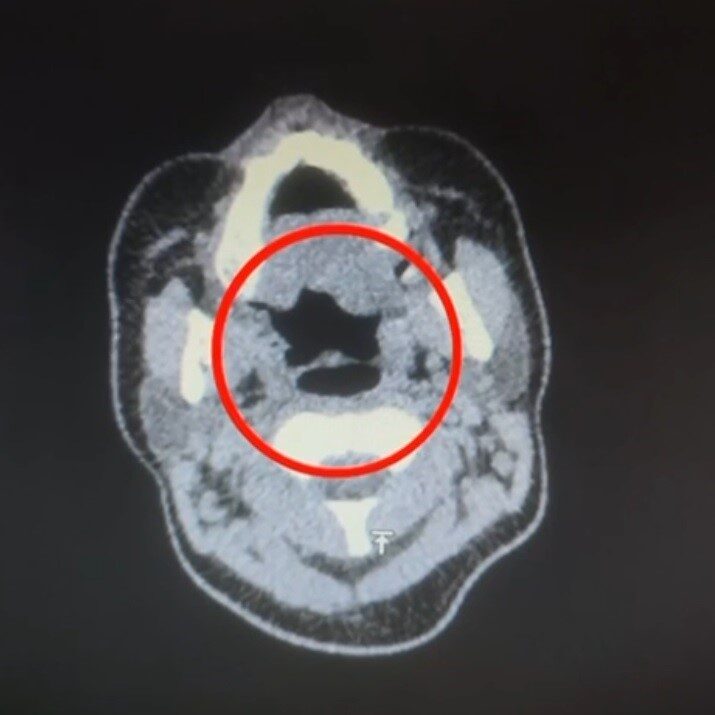

Yapılan iç beden muayenesinde A.R.’nin midesinde toplamda 50 tane kapsül halinde uyuşturucu madde bulunduğu tespit edildi. Bu kapsüllerin toplam ağırlığı ise 500 gram olarak belirlendi.